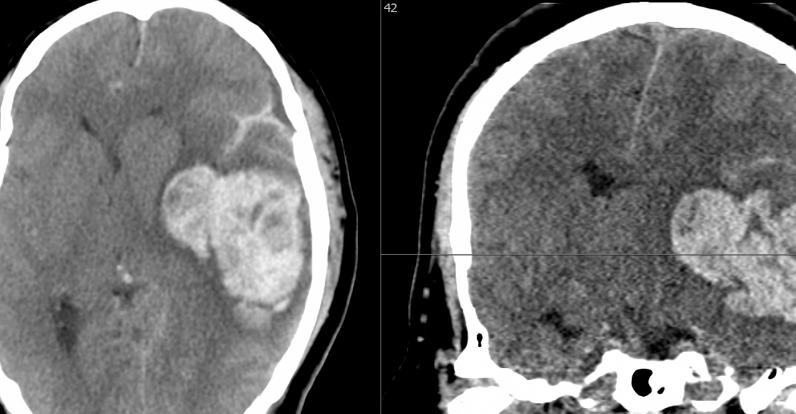

En TC realizado en la urgencia se observa hematoma intraparenquimatoso temporal izquierdo que desplaza 16 mm las estructuras de línea media y produce herniación uncal izquierda (imagen 1).